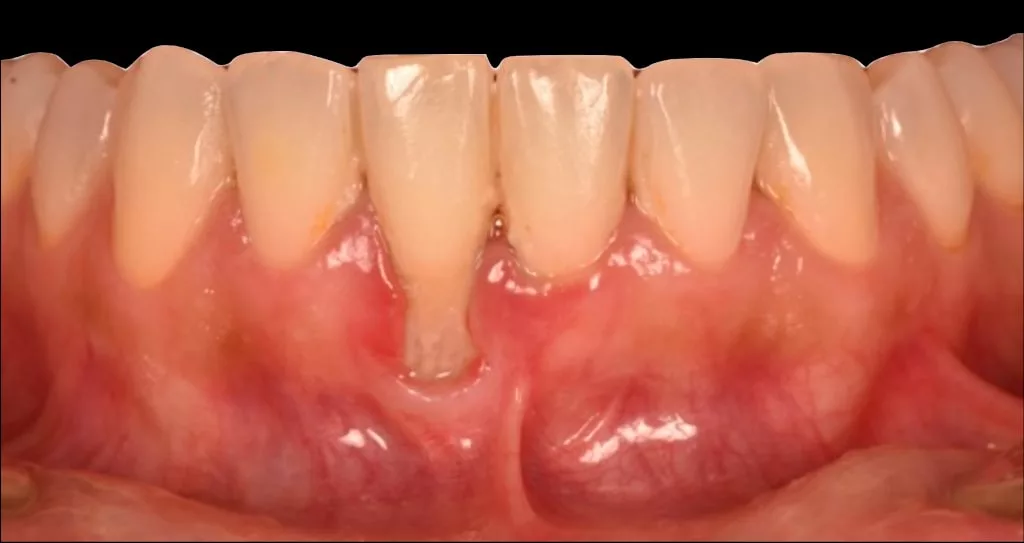

L’un des symptômes de la maladie parodontale est la visibilité des racines des dents par rétractation des gencives, également appelée récession gingivale.

Cette dénudation de la surface dentaire peut également intervenir en cas de frottement mécanique trop intense au niveau de la zone, par exemple avec un brossage traumatique.